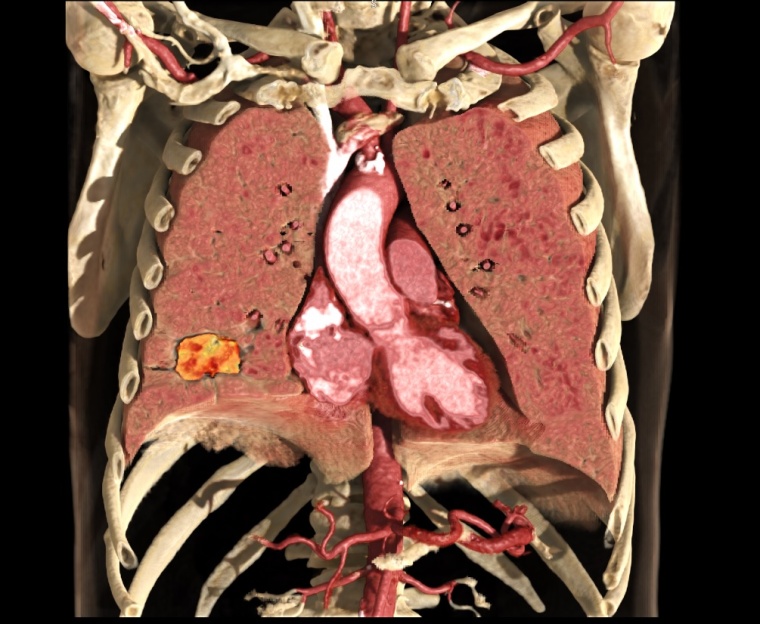

Dank künstlicher Intelligenz und neuer 3D-Rendering-Technik ist ein fotorealistischer Blick auf die Anatomie möglich.

Global Illumination von Canon Medical ist eine neue innovative 3D-Rendering-Technik, die einen präzisen und fotorealistischen Blick auf die Anatomie ermöglicht. Mittels dieses hochqualitativen alternativen Blickeindruckes wird die Diskussion unter Ärzten, mit Patienten und weiteren Gesprächspartnern (z. B. der Gerichtsmedizin) einfacher und effizienter, da die Befunde plastischer erscheinen und leichter verständlich sind. Die einfach zu bedienende Software erzeugt fotorealistische Bilder und Videos, sie wurde kürzlich erstmals der Weltöffentlichkeit im Detail vorgestellt und ist für die Vitrea-Software von Canon Medical erhältlich.

Die künstliche Intelligenz und Deep-Learning sind in aller Munde. Canon Medical hat AiCE (Advanced Intelligent Clear-IQ Engine), den Deep Learning Rekonstruktionsalgorithmus für die CT-Rekonstruktion kürzlich erstmals der Weltöffentlichkeit präsentiert. AiCE beinhaltet ein neuronales Netz, welches in der Lage ist, das Bild-Rauschen in CT-Bildern von den eigentlichen Signalen zu differenzieren bzw. zu bereinigen. Damit werden CT-Bilder von außerordentlich hoher Qualität bei minimalem Rauschen und somit minimaler Dosis erzeugt.

Die Einführung des Ultra-High-Resolution-CT Aquilion Precision durch Canon Medical, der eine doppelte Auflösung von 150 µm bietet, war ein besonderer Anlass, die CT-Bild-Rekonstruktion der nächsten Generation zu entwickeln. Für eine ultrahochauflösende Bildgebung braucht man einen Algorithmus, der in der Lage ist, sehr schnell zu sein und zudem eine außerordentliche Detailgenauigkeit zu liefern. AiCE bietet nicht nur eine besonders hohe räumliche Auflösung, AiCE optimiert gleichzeitig die Niedrigkontrastauflösung der Bilder des Aquilion Precision CTs – und das bei vergleichbar niedriger Dosis. Die Kombination aus AiCE und dem UHR-CT Aquilion Precision definiert ein neues Kapitel in der CT.

Das ultrahochauflösende Scannen in Verbindung mit der Deep-Learning-Rekonstruktion wird die Bedeutung der CT in der Diagnostik bei einer Vielzahl von Fragestellungen weiter ausbauen. Klinische Anwendungen wie Darstellungen von z. B. Lunge, Gefäßsystem, Stentstruktur oder auch die Darstellung kleiner Tumoren und Veränderungen können allesamt von der neuen Qualität profitieren.

Die integrierte, effiziente und benutzerfreundliche AiCE Deep-Learning-Rekonstruktion sorgt dafür, dass die Welt der ultrahochauflösenden Computertomographie von den Fähigkeiten des Deep-Learning besonders profitiert. Neue Rendering-Tools für die Visualisierung erleichtern den Umgang mit der Vielzahl radiologischer Daten wie die Kommunikation mit allen Beteiligten. Die Kombination des Aquilion Precision und der AiCE DLR bietet signifikante Fortschritte bei der Diagnostik, den klinischen Anwendungen, wie auch der Radionomics und definiert die Zukunft der Computertomographie.